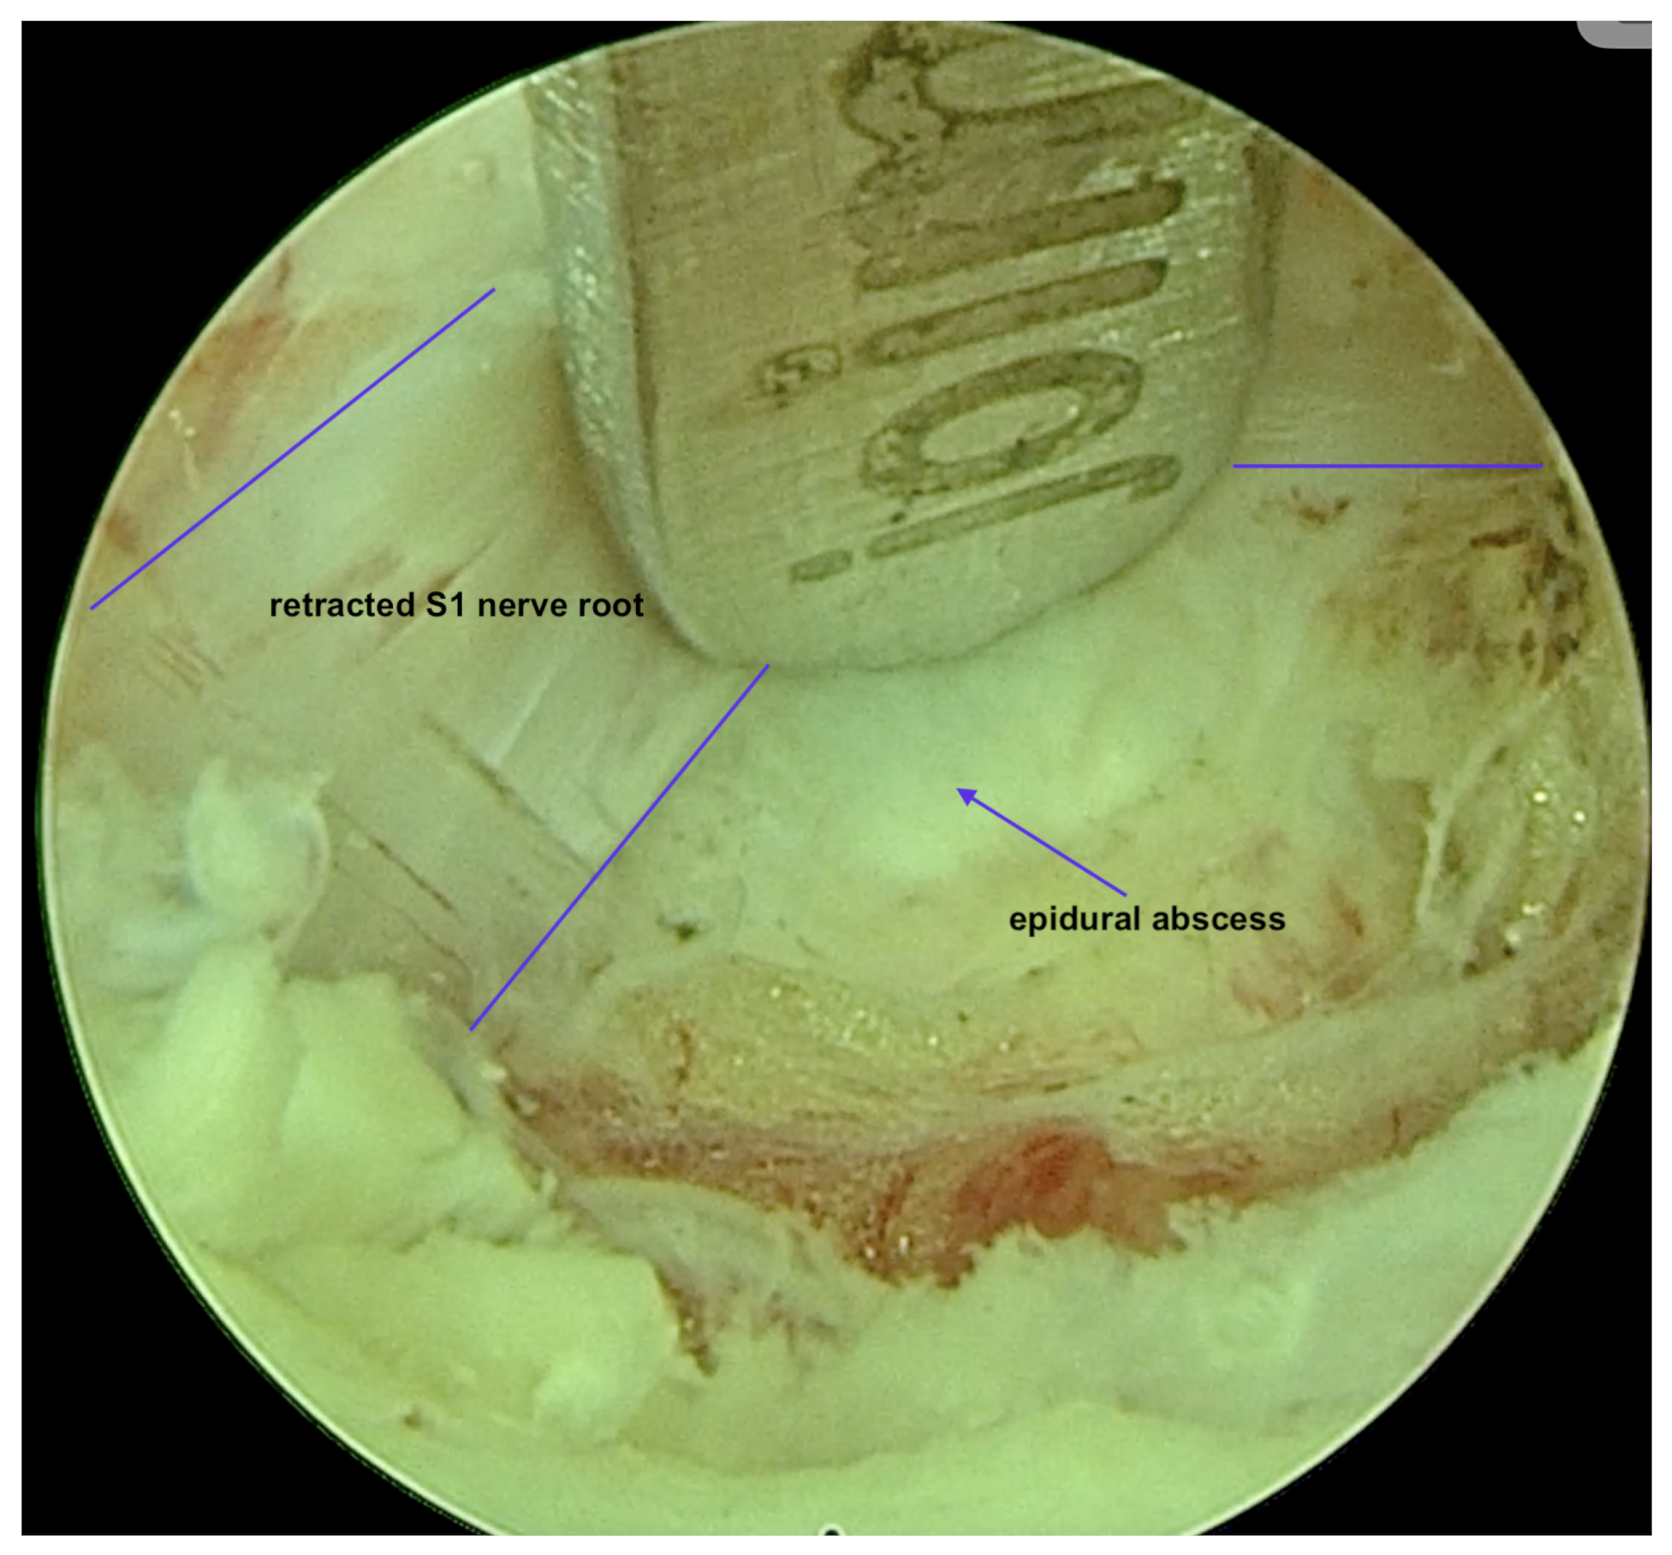

Diagnostic Evolution: After a week of conservative treatment without improvement, a follow-up MRI was ordered(Figure 3), which unambiguously identified spondylodiscitis with an abscess in the canal, causing compression of the dural sac and both S1 nerves (Figure 4). The patient’s pain syndrome worsened significantly, VAS 9 in the lower spine, leading to her qualification for surgical treatment.

Surgical Intervention: The patient underwent an Interlaminar Endoscopic Lumbar Discectomy (IELD) with slight dilation of the right inferior articular process of L5. A minor fenestration of the ligamentum flavum was performed. Inflammatory granulation masses, which were pressing under the root and dural sac, were removed for culture (Figure 5). The procedure revealed a freely pulsating dural sac, indicating successful decompression. Subsequently, percutaneous transpedicular stabilization of L5/S1 was executed. Post-operatively, the patient reported a significant reduction in pain symptoms. Follow-up MRI showed a reduction in inflammatory changes.

Figure 5. Intra-operative view of a fully endoscopic debridement of an epidural abscess.